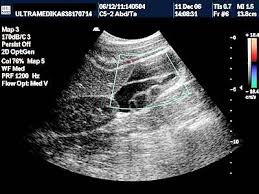

Ciste ometaju oplodnju.Mnogo toga zavisi od dosadnih cisti,koje počesto sprječavaju žene da postanu majke.A kako ih se riješiti?